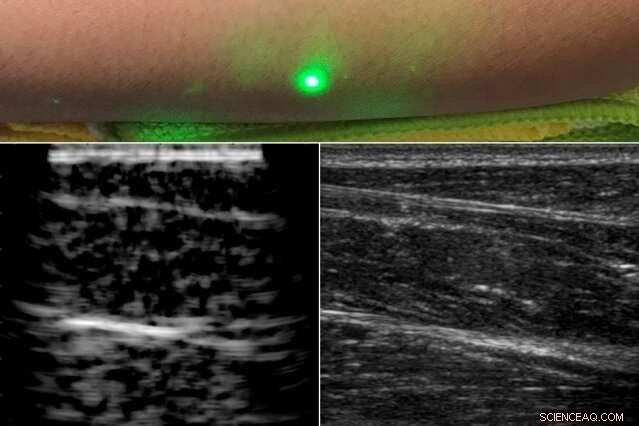

A new ultrasound technique uses lasers to produce images beneath the skin, without making contact with the skin as conventional ultrasound probes do. The new laser ultrasound technique was used to produce an image (left) of a human forearm (above), which was also imaged using conventional ultrasound (right). Credit: Massachusetts Institute of Technology

In a paper published today by Nature in the journal Light: Science and Applications, the team reports generating the first laser ultrasound images in humans. The researchers scanned the forearms of several volunteers and observed common tissue features such as muscle, fat, and bone, down to about 6 centimeters below the skin. These images, comparable to conventional ultrasound, were produced using remote lasers focused on a volunteer from half a meter away.

Finally, the team carried out the first laser ultrasound experiments in humans, using a protocol that was approved by the MIT Committee on the Use of Humans as Experimental Subjects. After scanning the forearms of several healthy volunteers, the researchers produced the first fully noncontact laser ultrasound images of a human. The fat, muscle, and tissue boundaries are clearly visible and comparable to images generated using commercial, contact-based ultrasound probes.